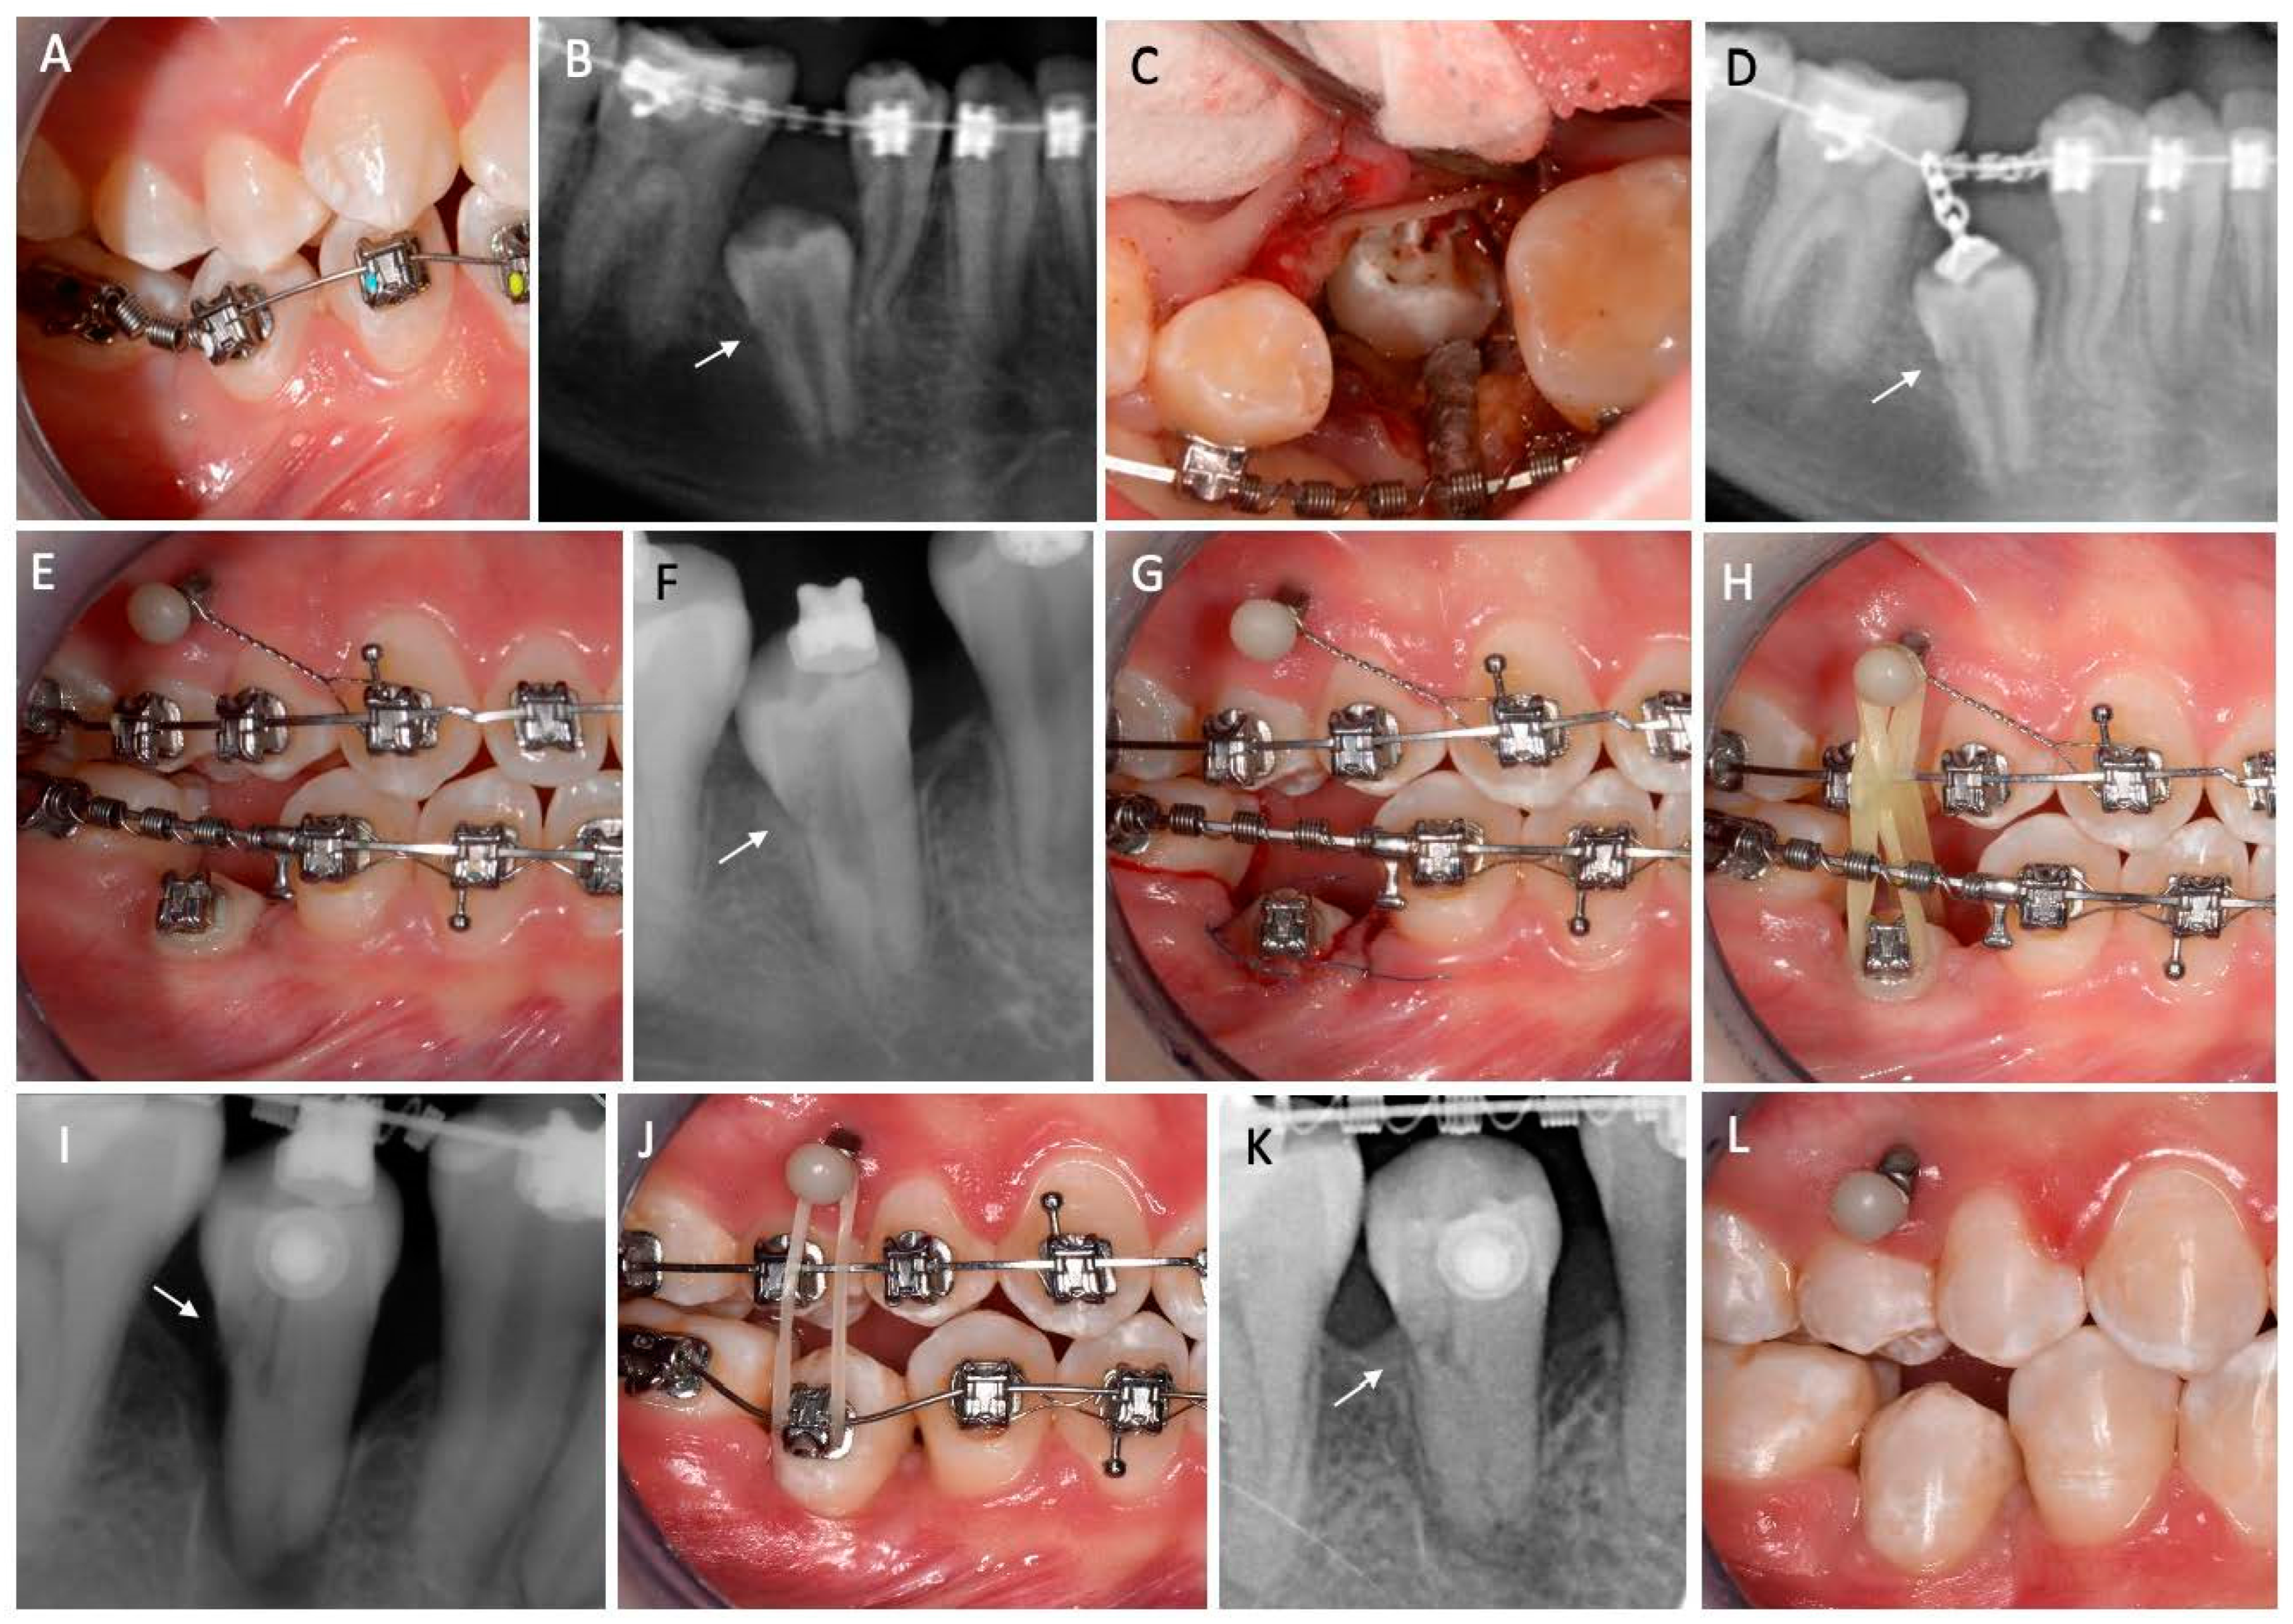

2. Case Presentation